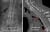

Болест на Бехтерев Изкривяване на гръбнака следствие от болест на Бехтерев Засягане на гръбначния стълб и сакроилиачните стави при болест на Бехтерев Начало и посока на расвитие при болест на Бехтерев Гръбнак тип "Бамбукова пръчка" и сливане на прешлени

Болест на БехтеревИзкривяване на гръбнака следствие от болест на БехтеревЗасягане на гръбначния стълб и сакроилиачните стави при болест на БехтеревНачало и посока на расвитие при болест на БехтеревГръбнак тип "Бамбукова пръчка" и сливане на прешлени